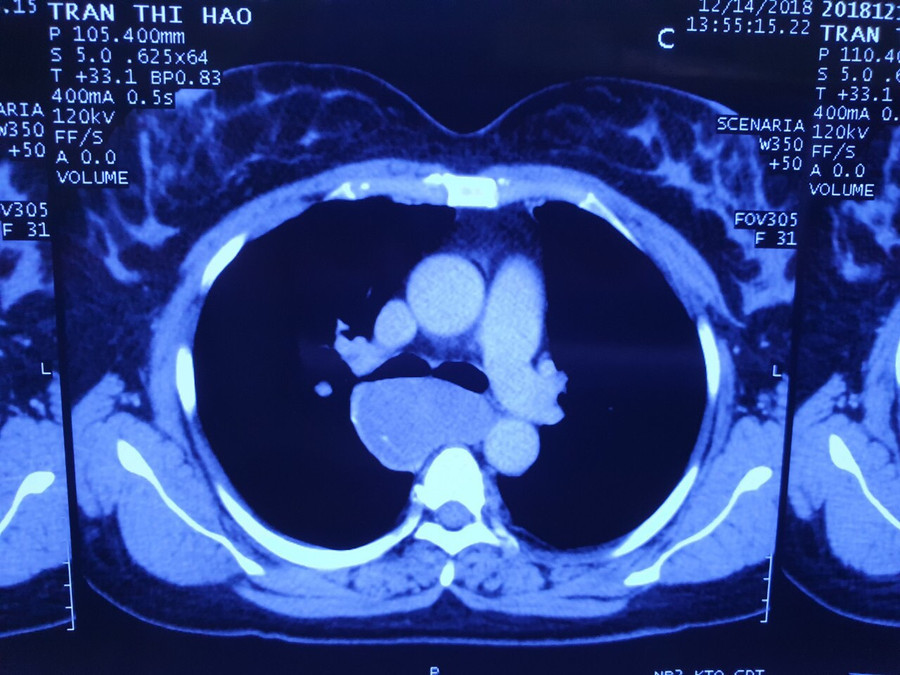

| Phim chụp khối u |

Sau khi được thăm khám, làm các chỉ định xét nghiệm, siêu âm, chụp CT lồng ngực và nội soi, các bác sĩ chẩn đoán bệnh nhân có u cơ lớn thực quản 8cm ôm quanh thực quản 1/3 trên.